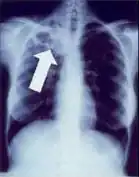

A tuberculose cria cavidades visíveis em radiografias como esta, na parte superior do pulmão direito.

Uma radiografia postero-anterior do tórax é a tradicionalmente feita; outras vistas (lateral ou lordótico) ou imagens de tomografia computadorizada podem ser necessárias.

Em tuberculose pulmonar ativa, infiltrações ou consolidações e/ou cavidades são frequentemente vistas na parte superior dos pulmões com ou sem linfadenopatia (doença nos nódulos linfáticos) mediastinal ou hilar. No entanto, lesões podem aparecer em qualquer lugar nos pulmões. Em pessoas com HIV e outras imunossupressões, qualquer anormalidade pode indicar a tuberculose, ou o raio-x dos pulmões pode até mesmo parecer inteiramente normal.